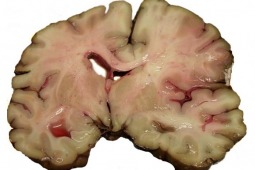

Brak wiedzy na temat udaru mózgu sprawia, że Polacy za późno wzywają pogotowie ratunkowe w razie wystąpienia jego objawów, takich jak np. zaburzenia mowy, jednostronny niedowład, zaburzenia czucia, asymetria twarzy.

-Jak tłumaczył, w tym tzw. złotym okresie pacjent powinien wezwać pogotowie i zostać przez nie zawieziony do szpitala z oddziałem udarowym (w jak najkrótszym czasie), gdzie konieczne jest jeszcze wykonanie u niego tomografii komputerowej głowy (TK), by wykluczyć krwotok oraz badań krwi, by wykluczyć inne choroby – pisze „Gazeta Wyborcza”. Dopiero wtedy lekarz może podjąć decyzję, czy choremu podać lek trombolityczny. Rozpuszcza on skrzeplinę, która zablokowała tętnicę prowadzącą krew do mózgu i wywołała niedokrwienie części tkanki nerwowej, czyli udar niedokrwienny. Stanowi on ok. 80-85 proc. wszystkich przypadków udaru; pozostałe 15 proc. to udary krwotoczne, będące skutkiem pęknięcia naczynia krwionośnego w mózgu.